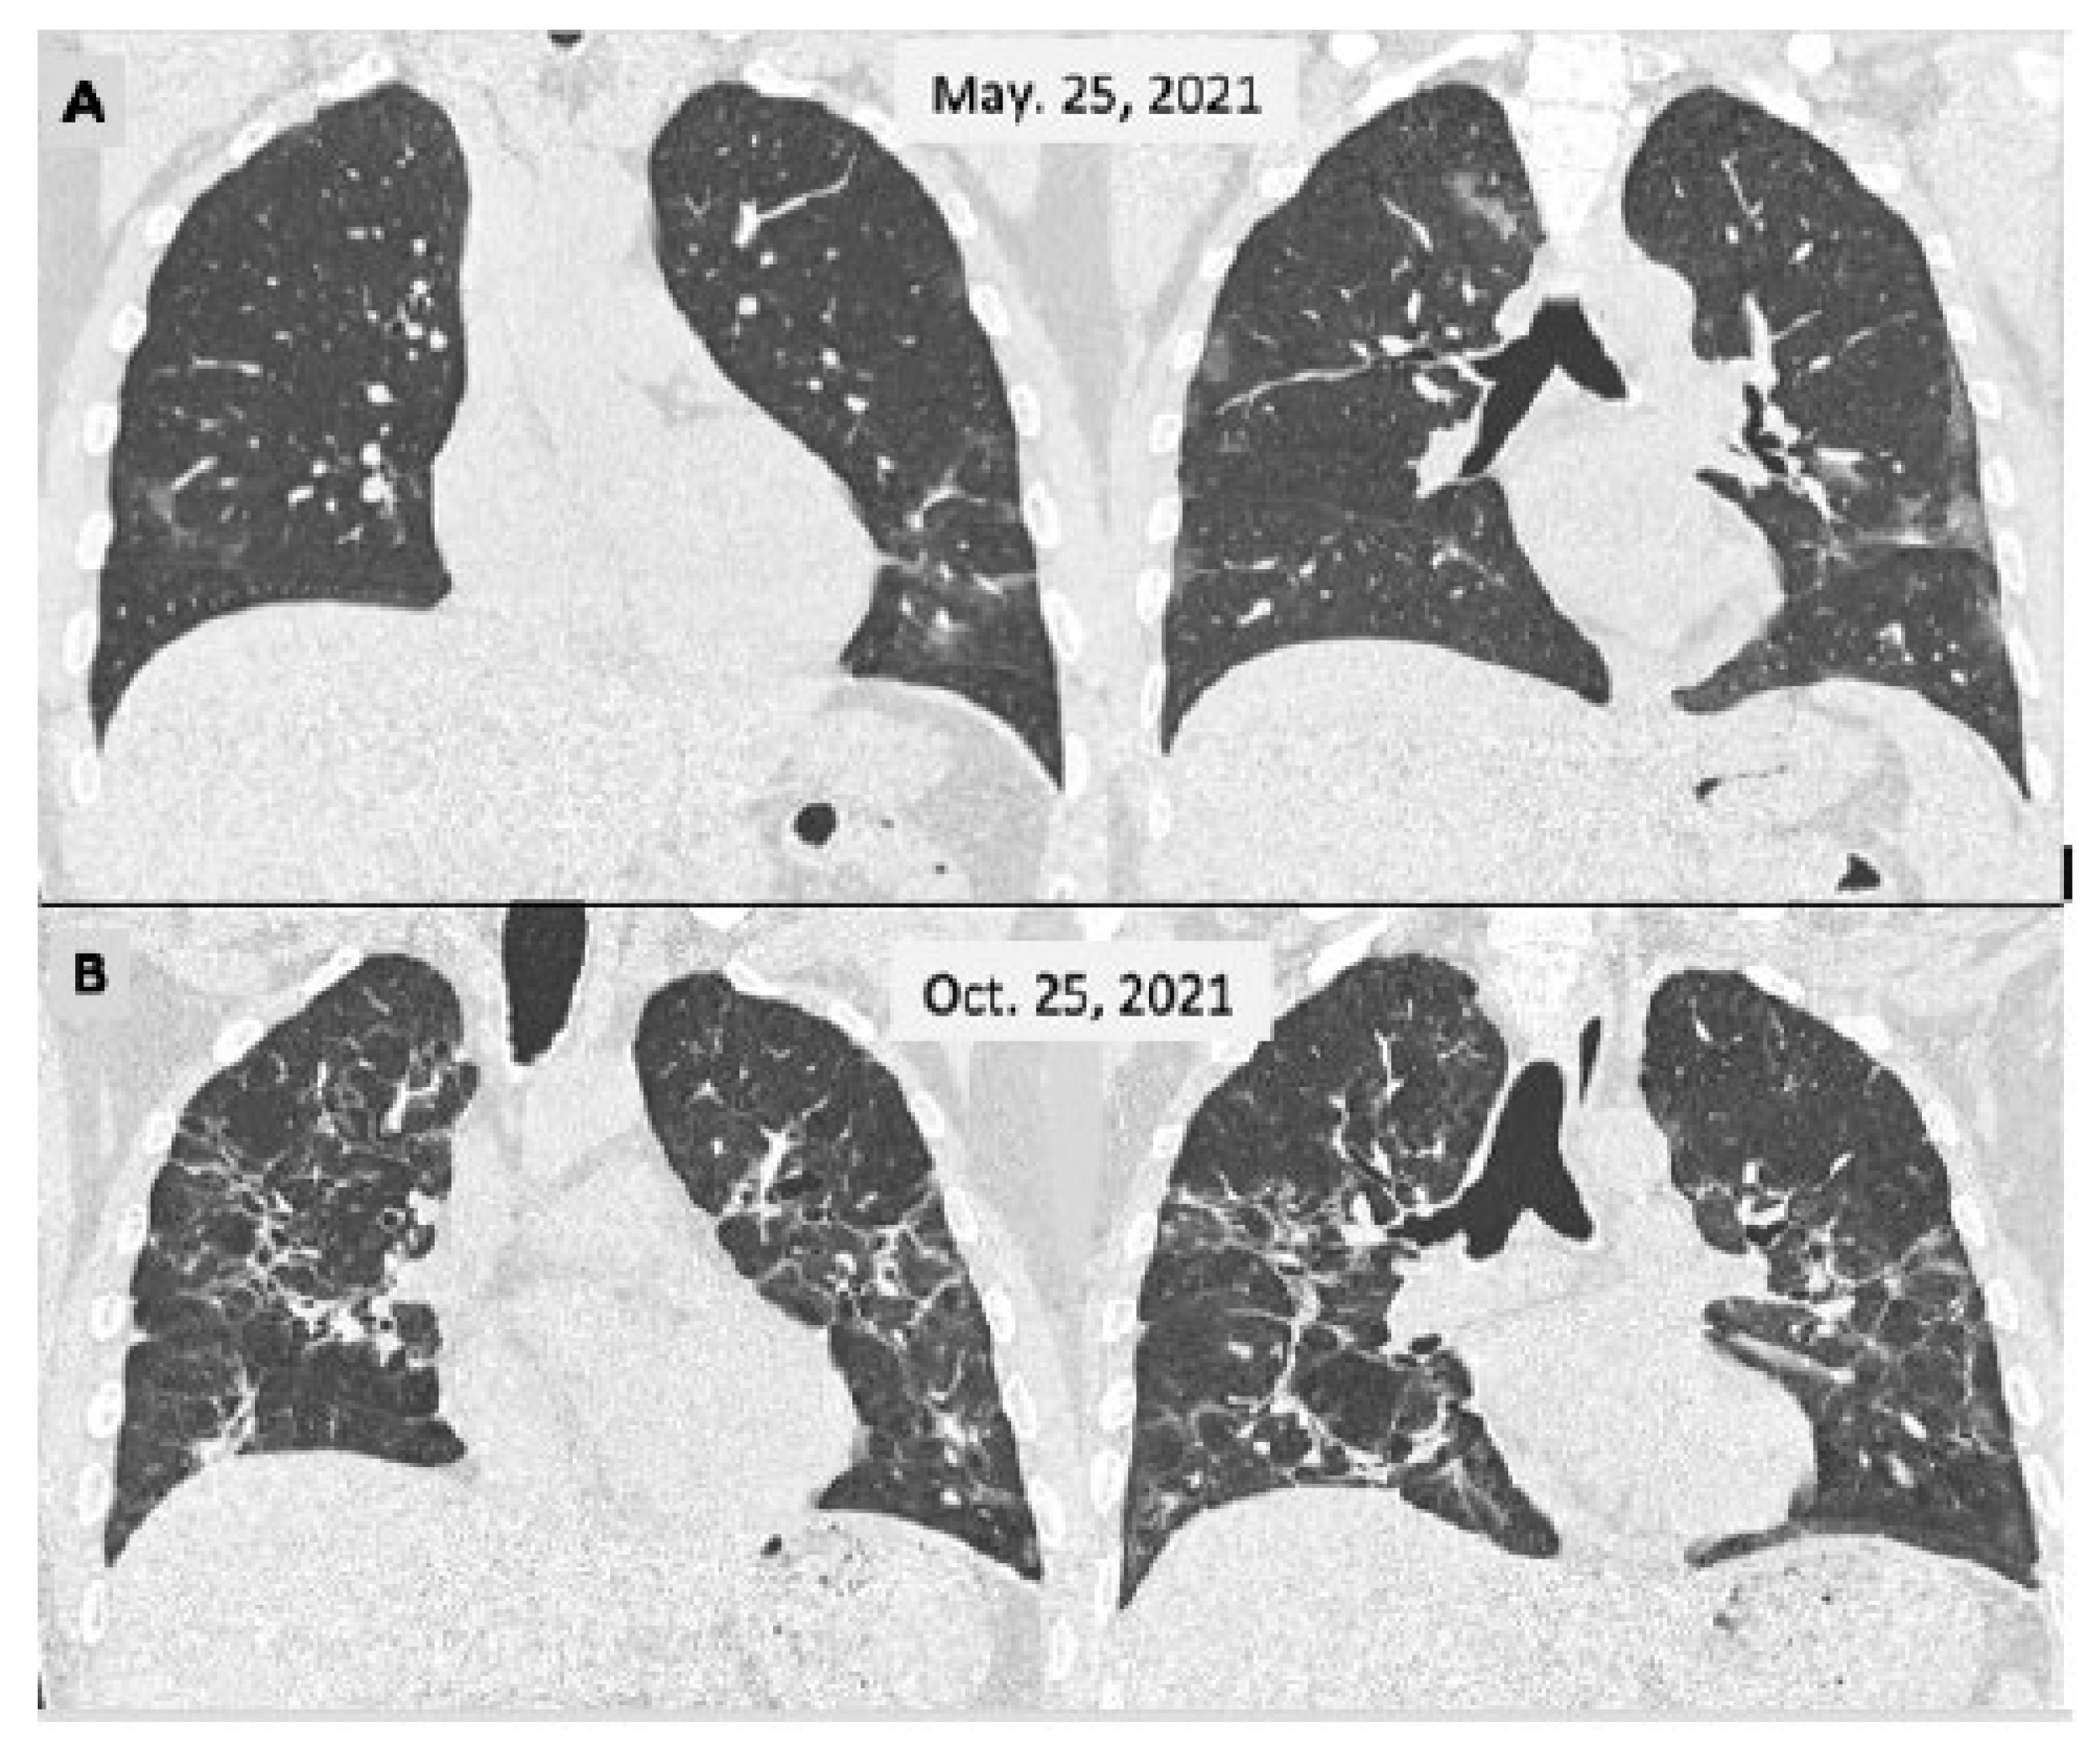

4. Pulmonary Domain